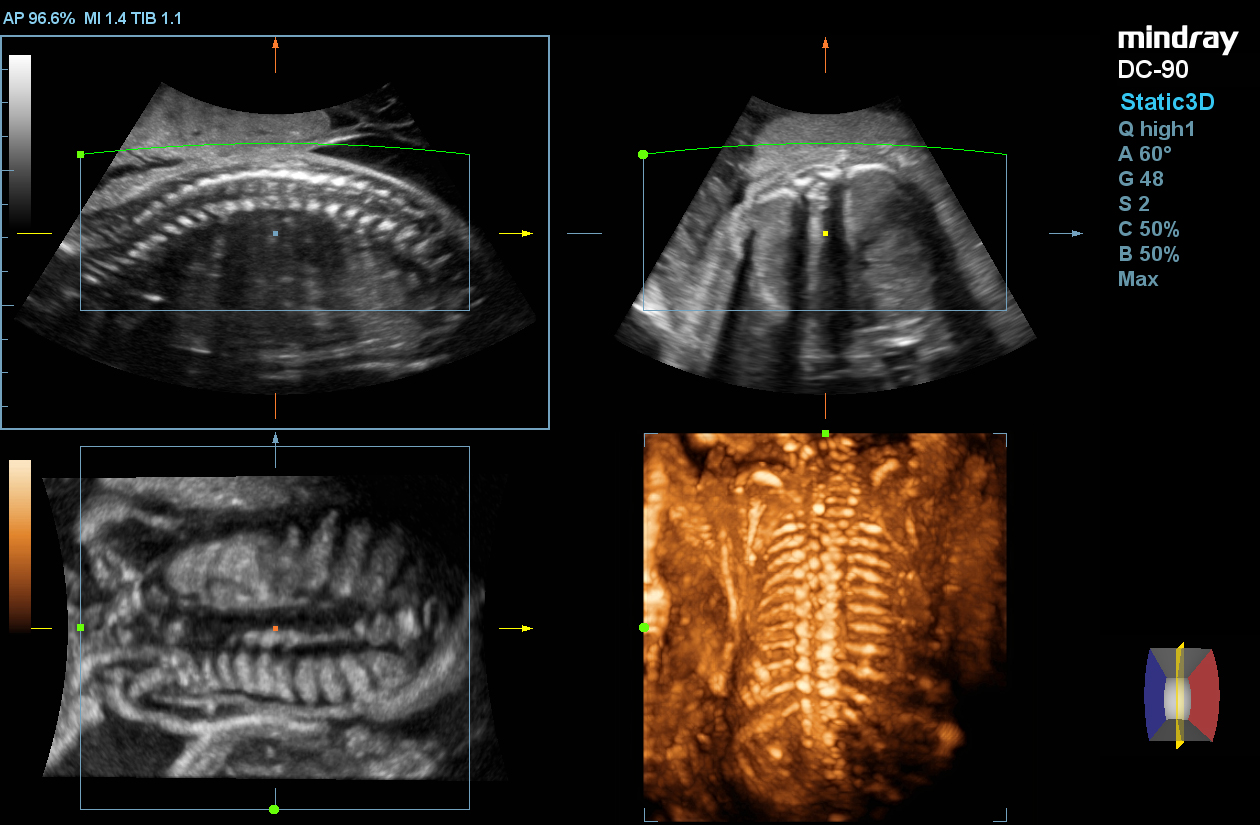

Smart Planes CNS

Smart Planes provides a robust and user-friendly solution to automatically detect planes and calculate frequently used measurements of the central nervous system (CNS) in fetal brain examinations.

Smart Face

Smart Face provides a fast and intelligent optimization for fetal face with simple one-touch operation. It can immediately remove occlusions such as cord, placenta, uterus, and extremities in the volume data, to generate an optimal view of the fetal face.